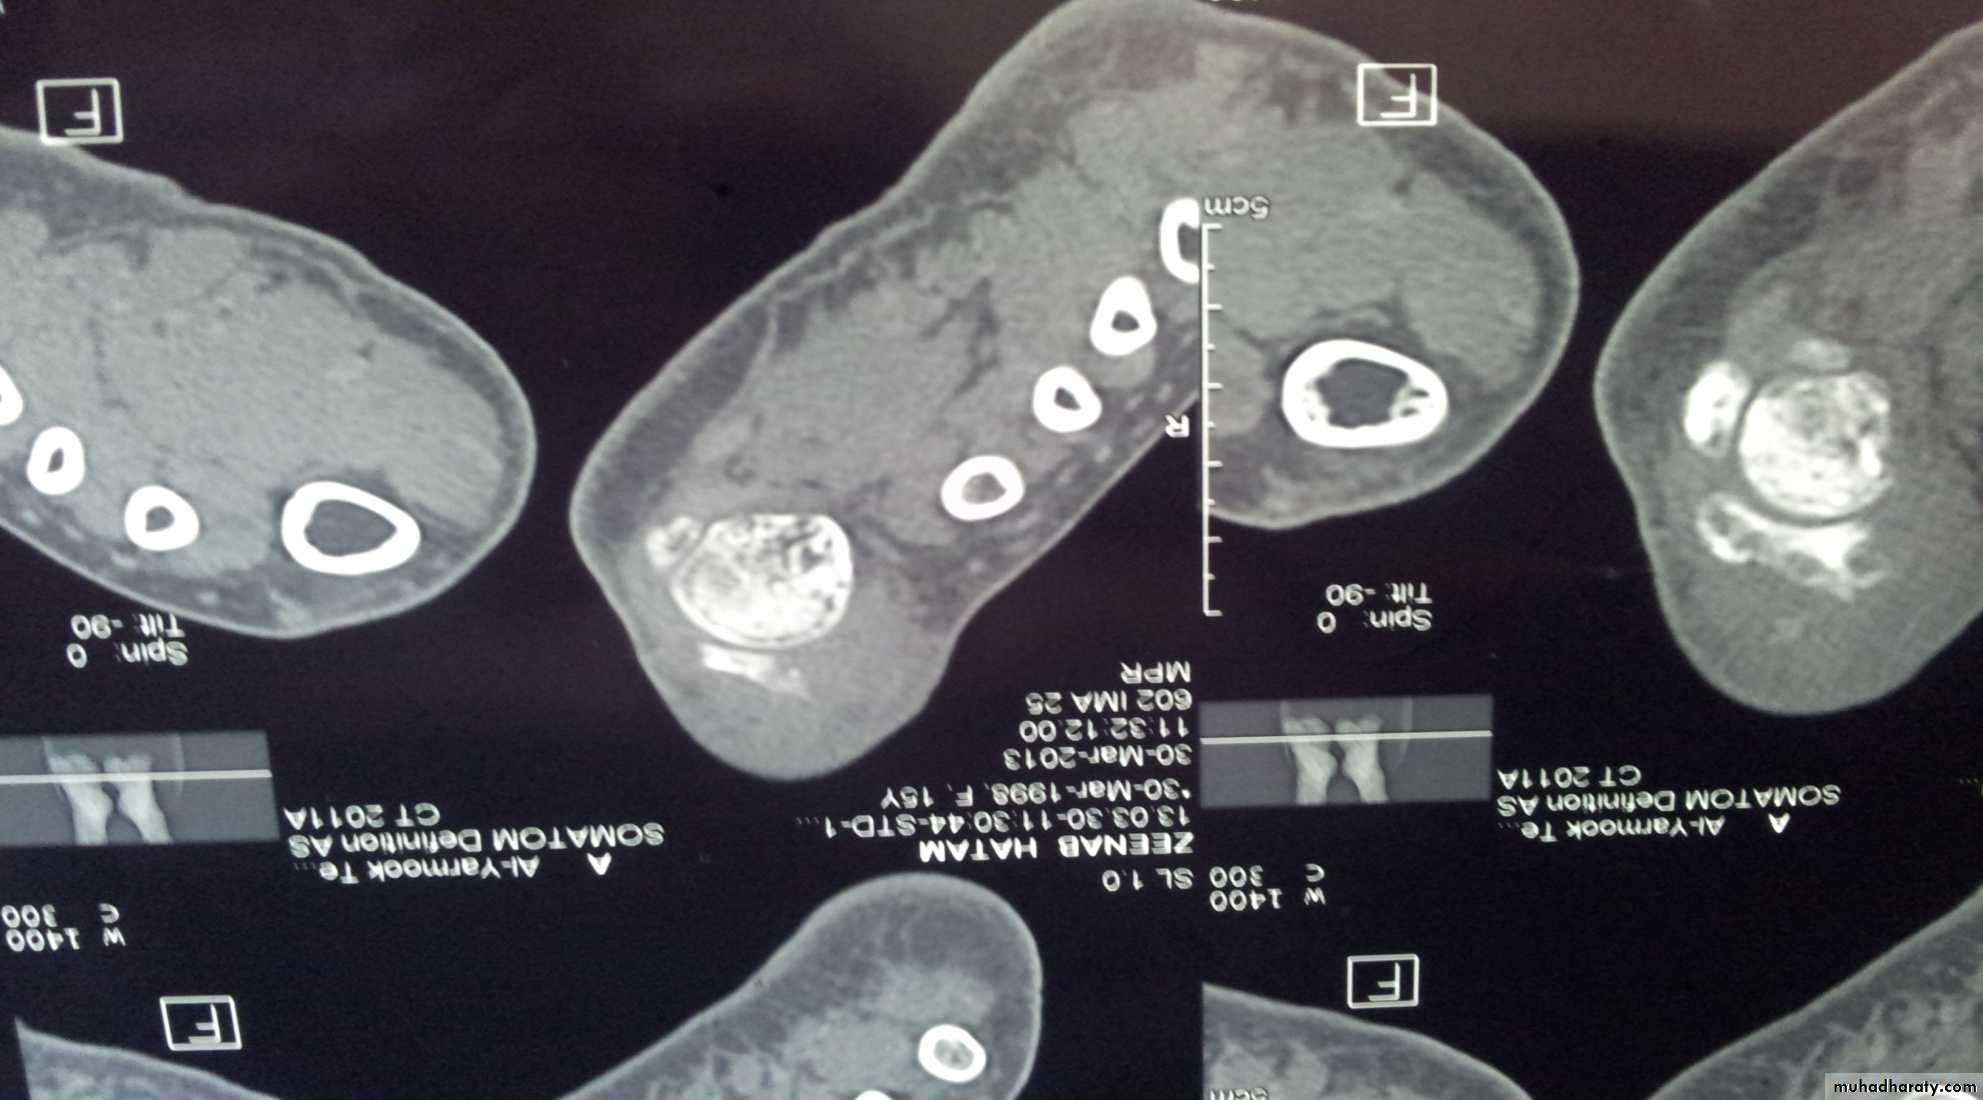

Imaging:

X-Ray: shows area of rarefaction surrounded by sclerosis.

And sometimes with sequestra.

Sinogram helpful to localize the site.

Bone scan: useful for revealing hidden foci of infection.